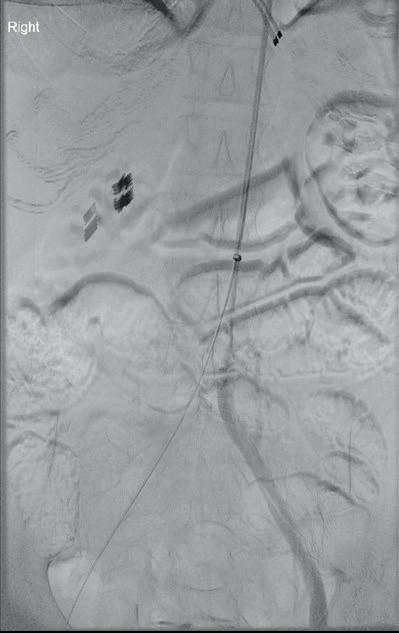

Left: Pre- and postoperative images (courtesy of Dittmar Böckler) of the first European implantation of the Gore Tag TBE; above: Dittmar Böckler performing the implantation